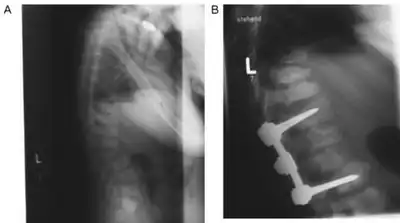

The first decade of life is characterised by the development of hearing impairment, psychomotor delay, recurrent infections, especially upper airway infections, pulmonary infections and acute/serous otitis media infections.[7] Significant changes in a number of facial features may occur, such as: protruding forehead; flattened nasal bridge; small nose; wide mouth; and widely spaced teeth.[2] Muscular weakness or spinal abnormalities can occur due to the build-up of storage materials in the muscle.[2]

There is no cure for congenital alpha-mannosidosis, and in general, the approach to management is proactive, with the aim of preventing emerging complications. After a full physical examination, physicians should focus on the known complications of alpha-mannosidosis, such as hydrocephalus, otitis media, hearing loss, dental caries, joint symptoms, kyphoscoliosis, and mental state.[2] Treatment is often limited to reducing or controlling the symptoms of the condition by, for example, medications to control seizures, hearing aids to ameliorate hearing loss, and routine physical therapy to assist with muscular pain and weakness.[2] In some cases, a wheelchair may be appropriate if muscle or spinal impairments immobilize the individual affected.